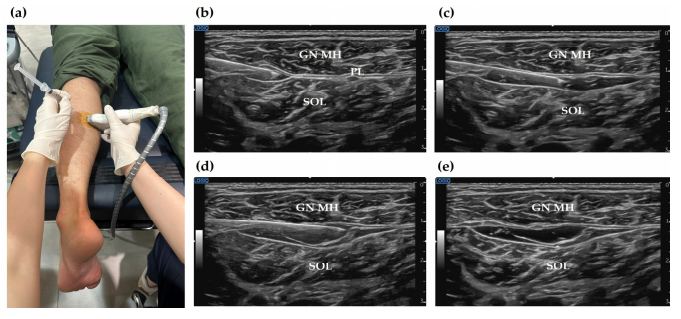

그 다음은 근막 통증 증후군입니다. 아킬레스건의 근육인 비복근(Gastrocnemius)과 가자미근(Soleus)의 길이가 짧아지면서, 아킬레스건을 잡아당기는 스트레스가 누적됩니다. 이러한 근육 긴장으로 근막통증증후군(MPS)이 유발될 수 있습니다.

한의학에서 근육, 근막은 "경근"이라고 하는데요. 눌렀을 때 가장 통증이 심한 혈자리를 찾아서 근육 사이 근막층에 약침을 주사하여 유착을 떼어냅니다. > 3단계: 신생혈관 신경성 염증 > > 만성 통증의 원인